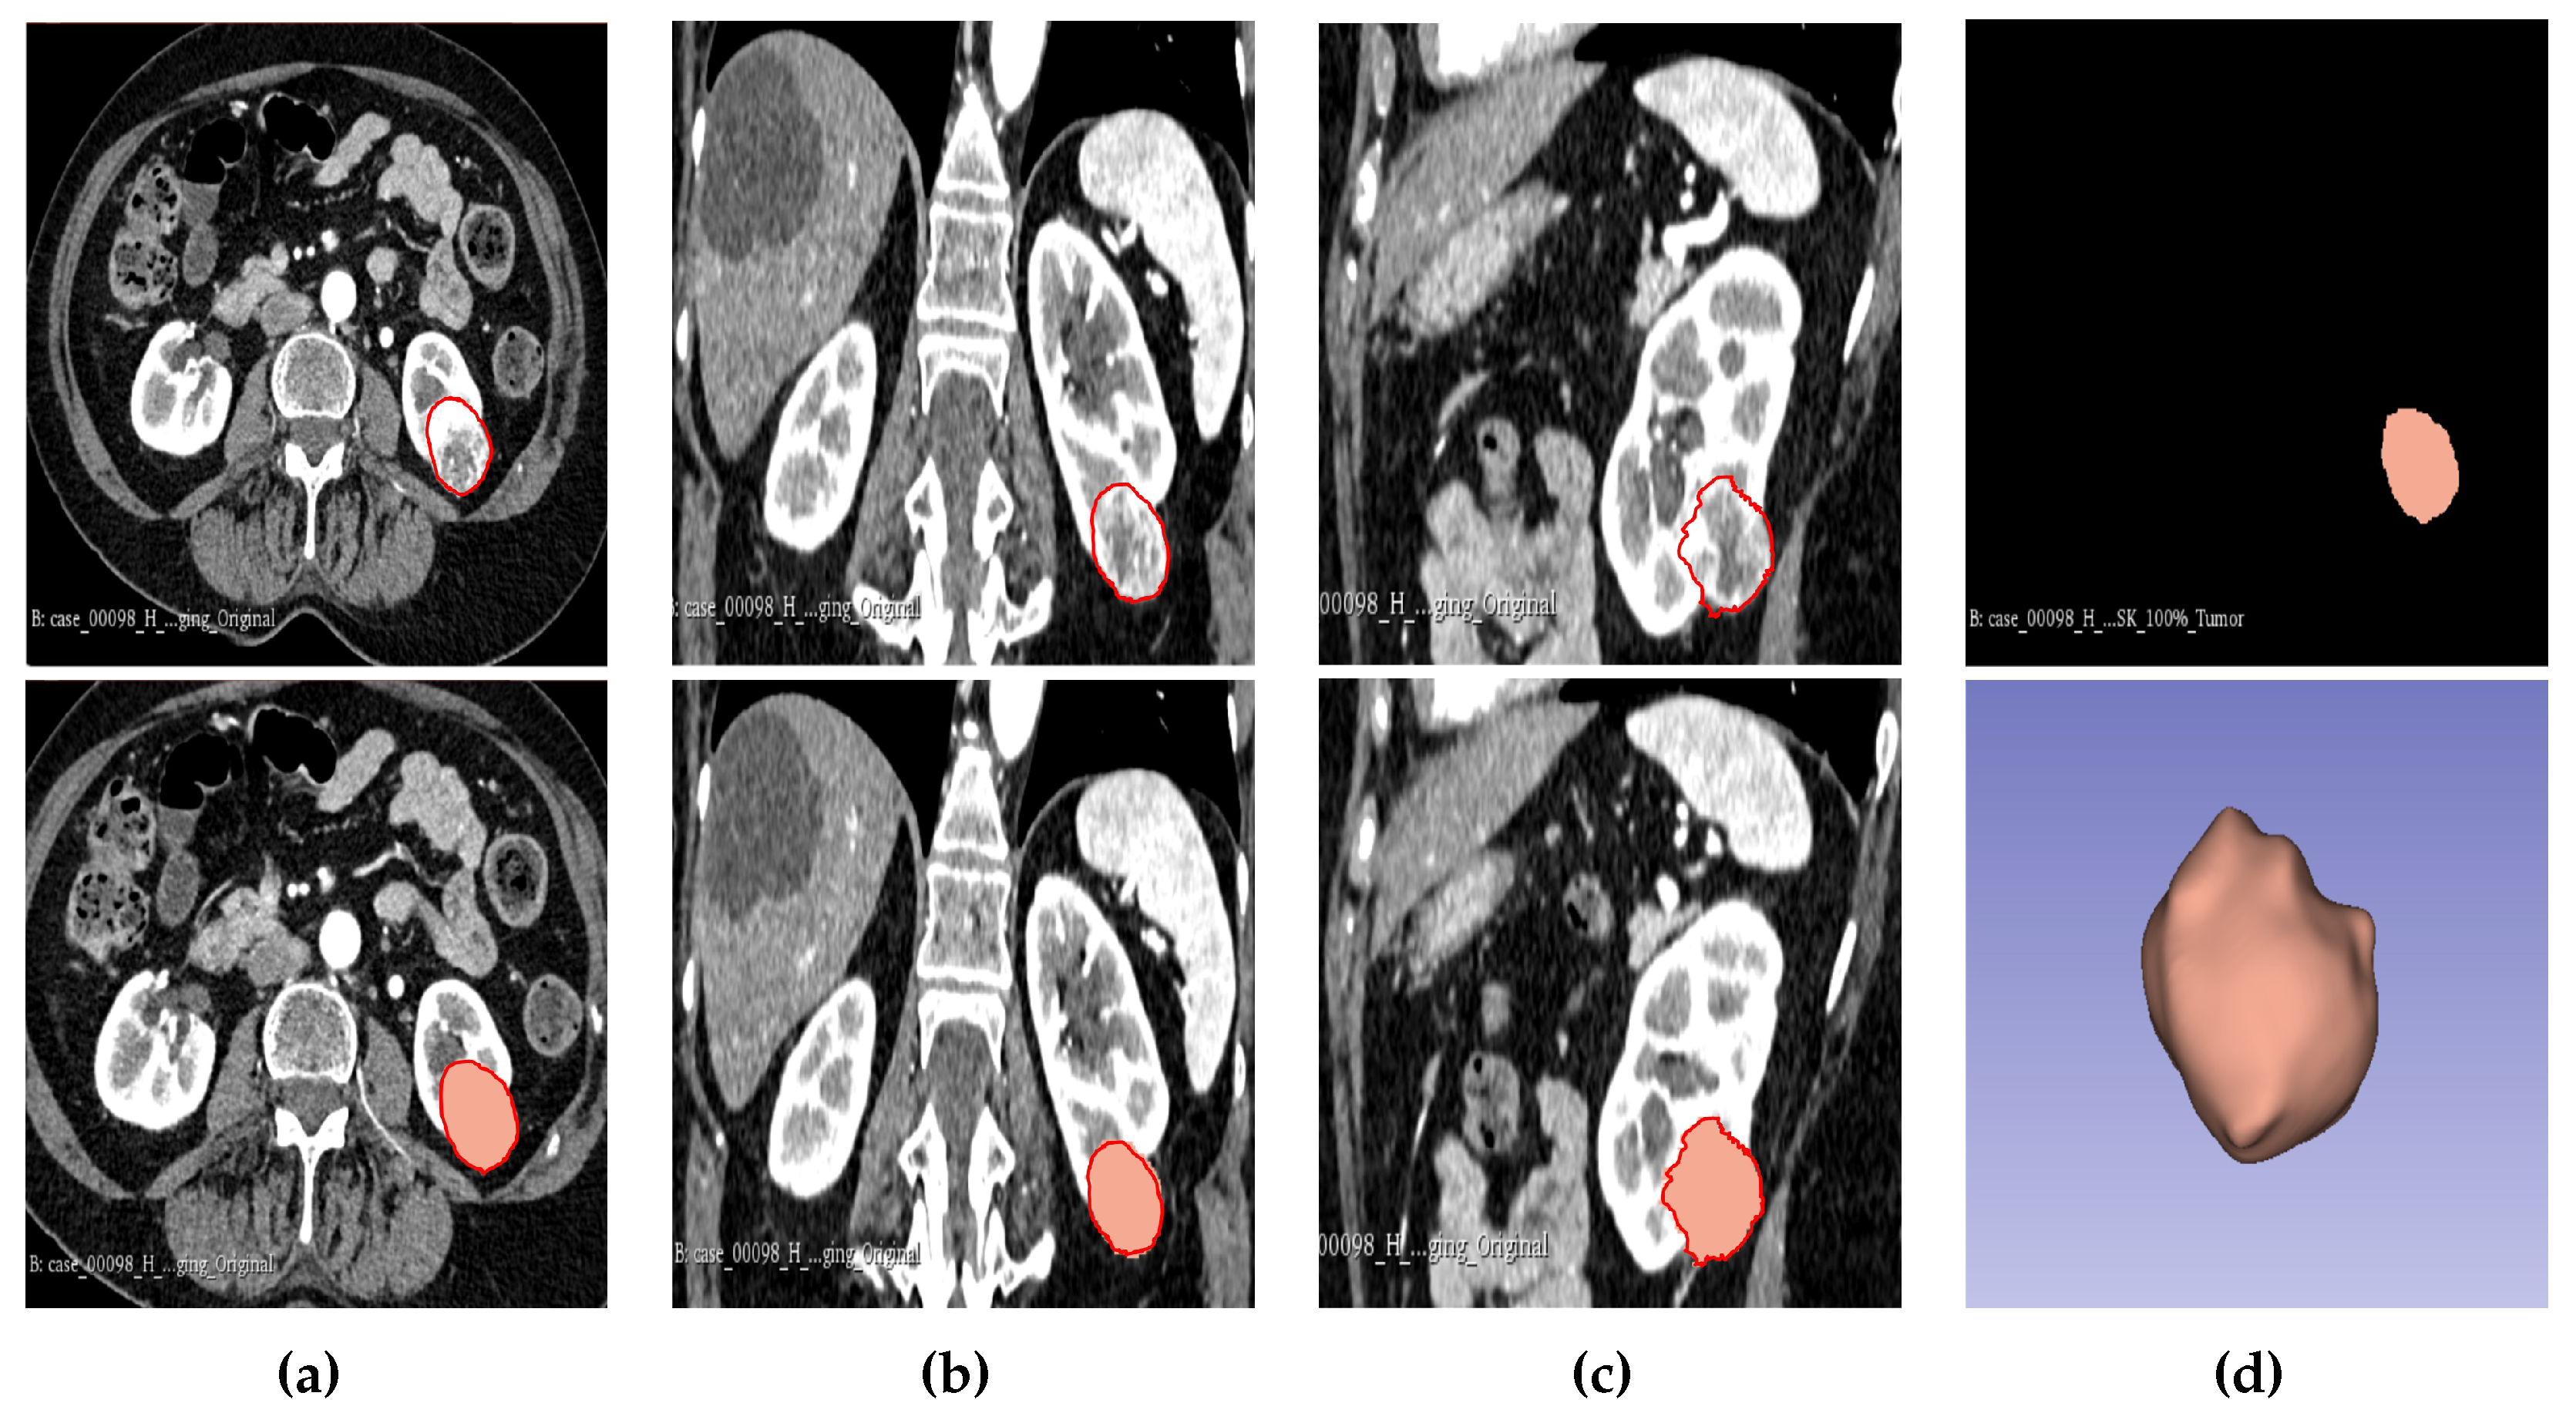

Figure 2. Manual segmentation of the 3D image slices using Slicer 3D software. (a) Axial plane of the tumour. (b) Coronal plane of the tumour. (c) Sagittal plane of the tumour. (d) Generated 3D VOI from the 2D slices delineated.

The result of the segmentation for both cohort 1 and 2 was a binary mask of the tumour. In the present study the tumour was divided into different subregions based on the geometry of the tumour i.e., periphery and core. The periphery refers to regions towards the edges of the tumour whereas the core represents regions close to the centre of the tumour. The core was obtained by extracting 25%, 50% and 75% of the binary mask from the centre of the tumour as shown in Figure 2, 3 and 4. The periphery was generated by extracting 25%, 50% and 75% of the binary mask starting from the edges of the tumour to form a rim as a hollow sphere as shown in fig2, fig3 and fig4. Mask generation was done using a python script which automatically generated the subregions through image subtraction techniques.